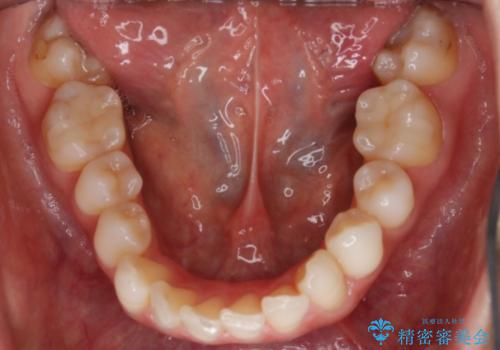

- 嚙み合わせのズレを主訴にご来院されました。

前歯・奥歯ともにセラミッククラウンで治療されている歯があったため、その歯にあまり影響が出ない範囲内で全体の噛み合わせが良くなるような動きを組み込んで治療を進めることとなりました。

矯正治療前にセラミック等の被せ物をされている場合、それ自体の外形は矯正治療では変更することができないため、その他の天然歯の移動に影響を与えてしまう場合があります。また、治療上設定されるアタッチメント(歯の表面に付けるプラスチックの突起)が付かない場合が多く、歯のコントロールが不足する場合があります。